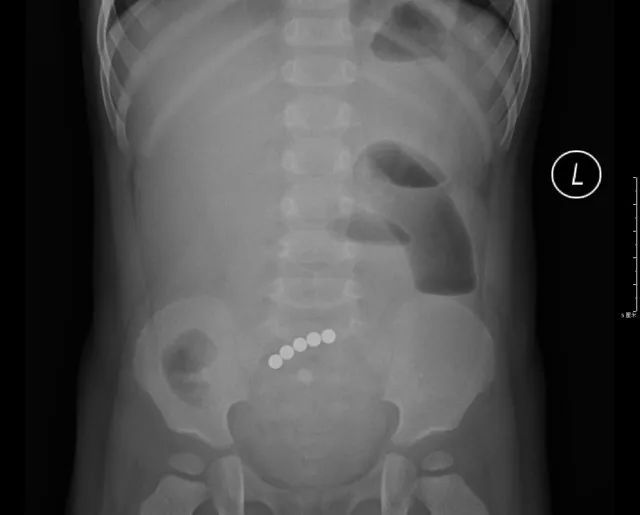

5个小球牢牢地吸在一起

打开腹腔后,医生终于找到了磁力球排不出来的原因:这5个小球分布在不同的肠段,但却牢牢地吸在一起。

医生小心地取出小磁球,再把穿孔的肠道切除,最后进行了缝合。整个手术足足花了2个小时。

手术中取出的5颗小磁球。